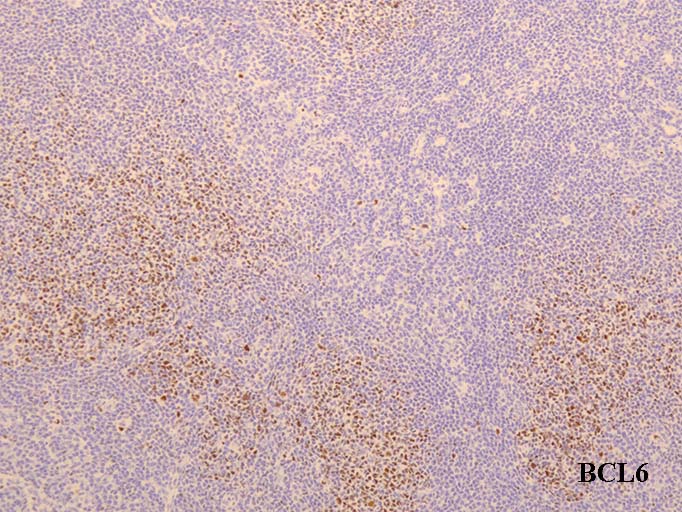

免疫染色

MIB-1(Ki67)-indexが低い濾胞は異常. CD10陽性細胞が濾胞辺縁や濾胞間にも見られるのは異常である---FL診断の重要な「必ずあってほしい~あってほしい所見」

MIB-1 labeling index(LI); 胚中心はlow. 濾胞外にCD10+細胞がこぼれている. 核型はt(14;18)の単独異常. 付加的異常はみられない.

Follicular lymphomaの免疫染色